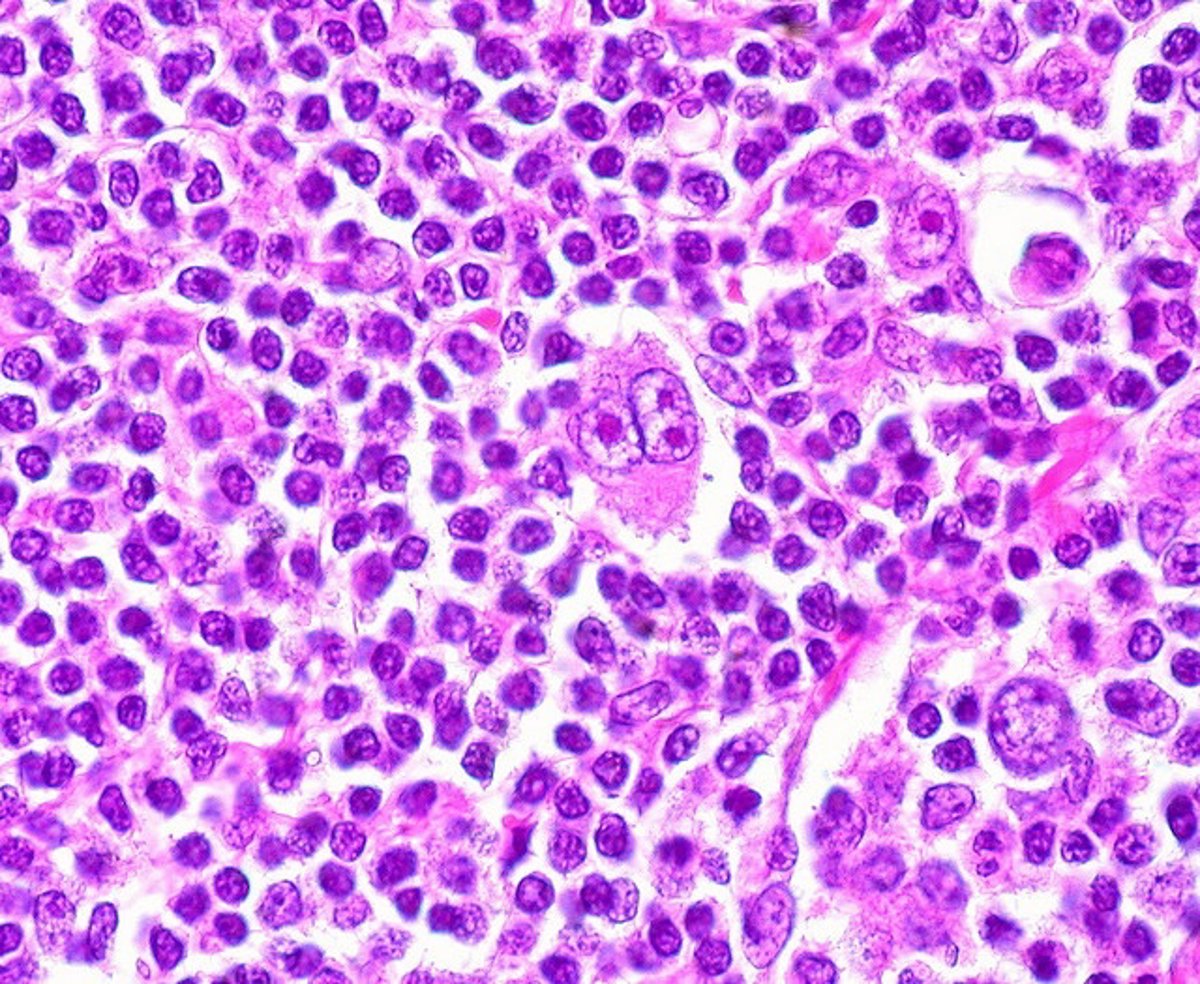

Linfoma de Hodking

FLICKR/ED UTHMAN

El Idival recuerda que un linfoma es una forma de cáncer que afecta al sistema inmunológico, específicamente, es un cáncer en las células defensivas del sistema inmunitario llamadas linfocitos.